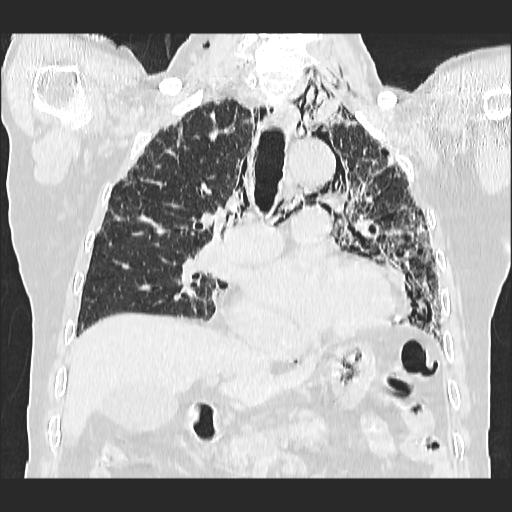

El parénquima pulmonar izquierdo muestra un infiltrado intersticial difuso que causa engrosamiento del septum axial, además del fenómeno de bronquiectasias quísticas se observan pequeñas bulas enfisematosas de localización subpleural que compromete ambas bases pulmonares.

Se observan imágenes de vidrio despulido en todo el lóbulo inferior izquierdo, el cual compromete los segmentos de la língula del segmento superior y medio

El parénquima pulmonar derecho muestra infiltrado intersticial en imagen de vidrio despulido con evidencia de lesiones subpleurales que representan bullas enfisematosas de diferentes tamaños.

Al utilizar un contraste Minip, se observan bronquiectasias cilíndricas en el extremo del lóbulo superior derecho, observándose un patrón de panal de abeja situada en la región apical del lóbulo superior izquierdo.

Bronquiectasias cilíndricas, bullas enfisematosas basales bilaterales